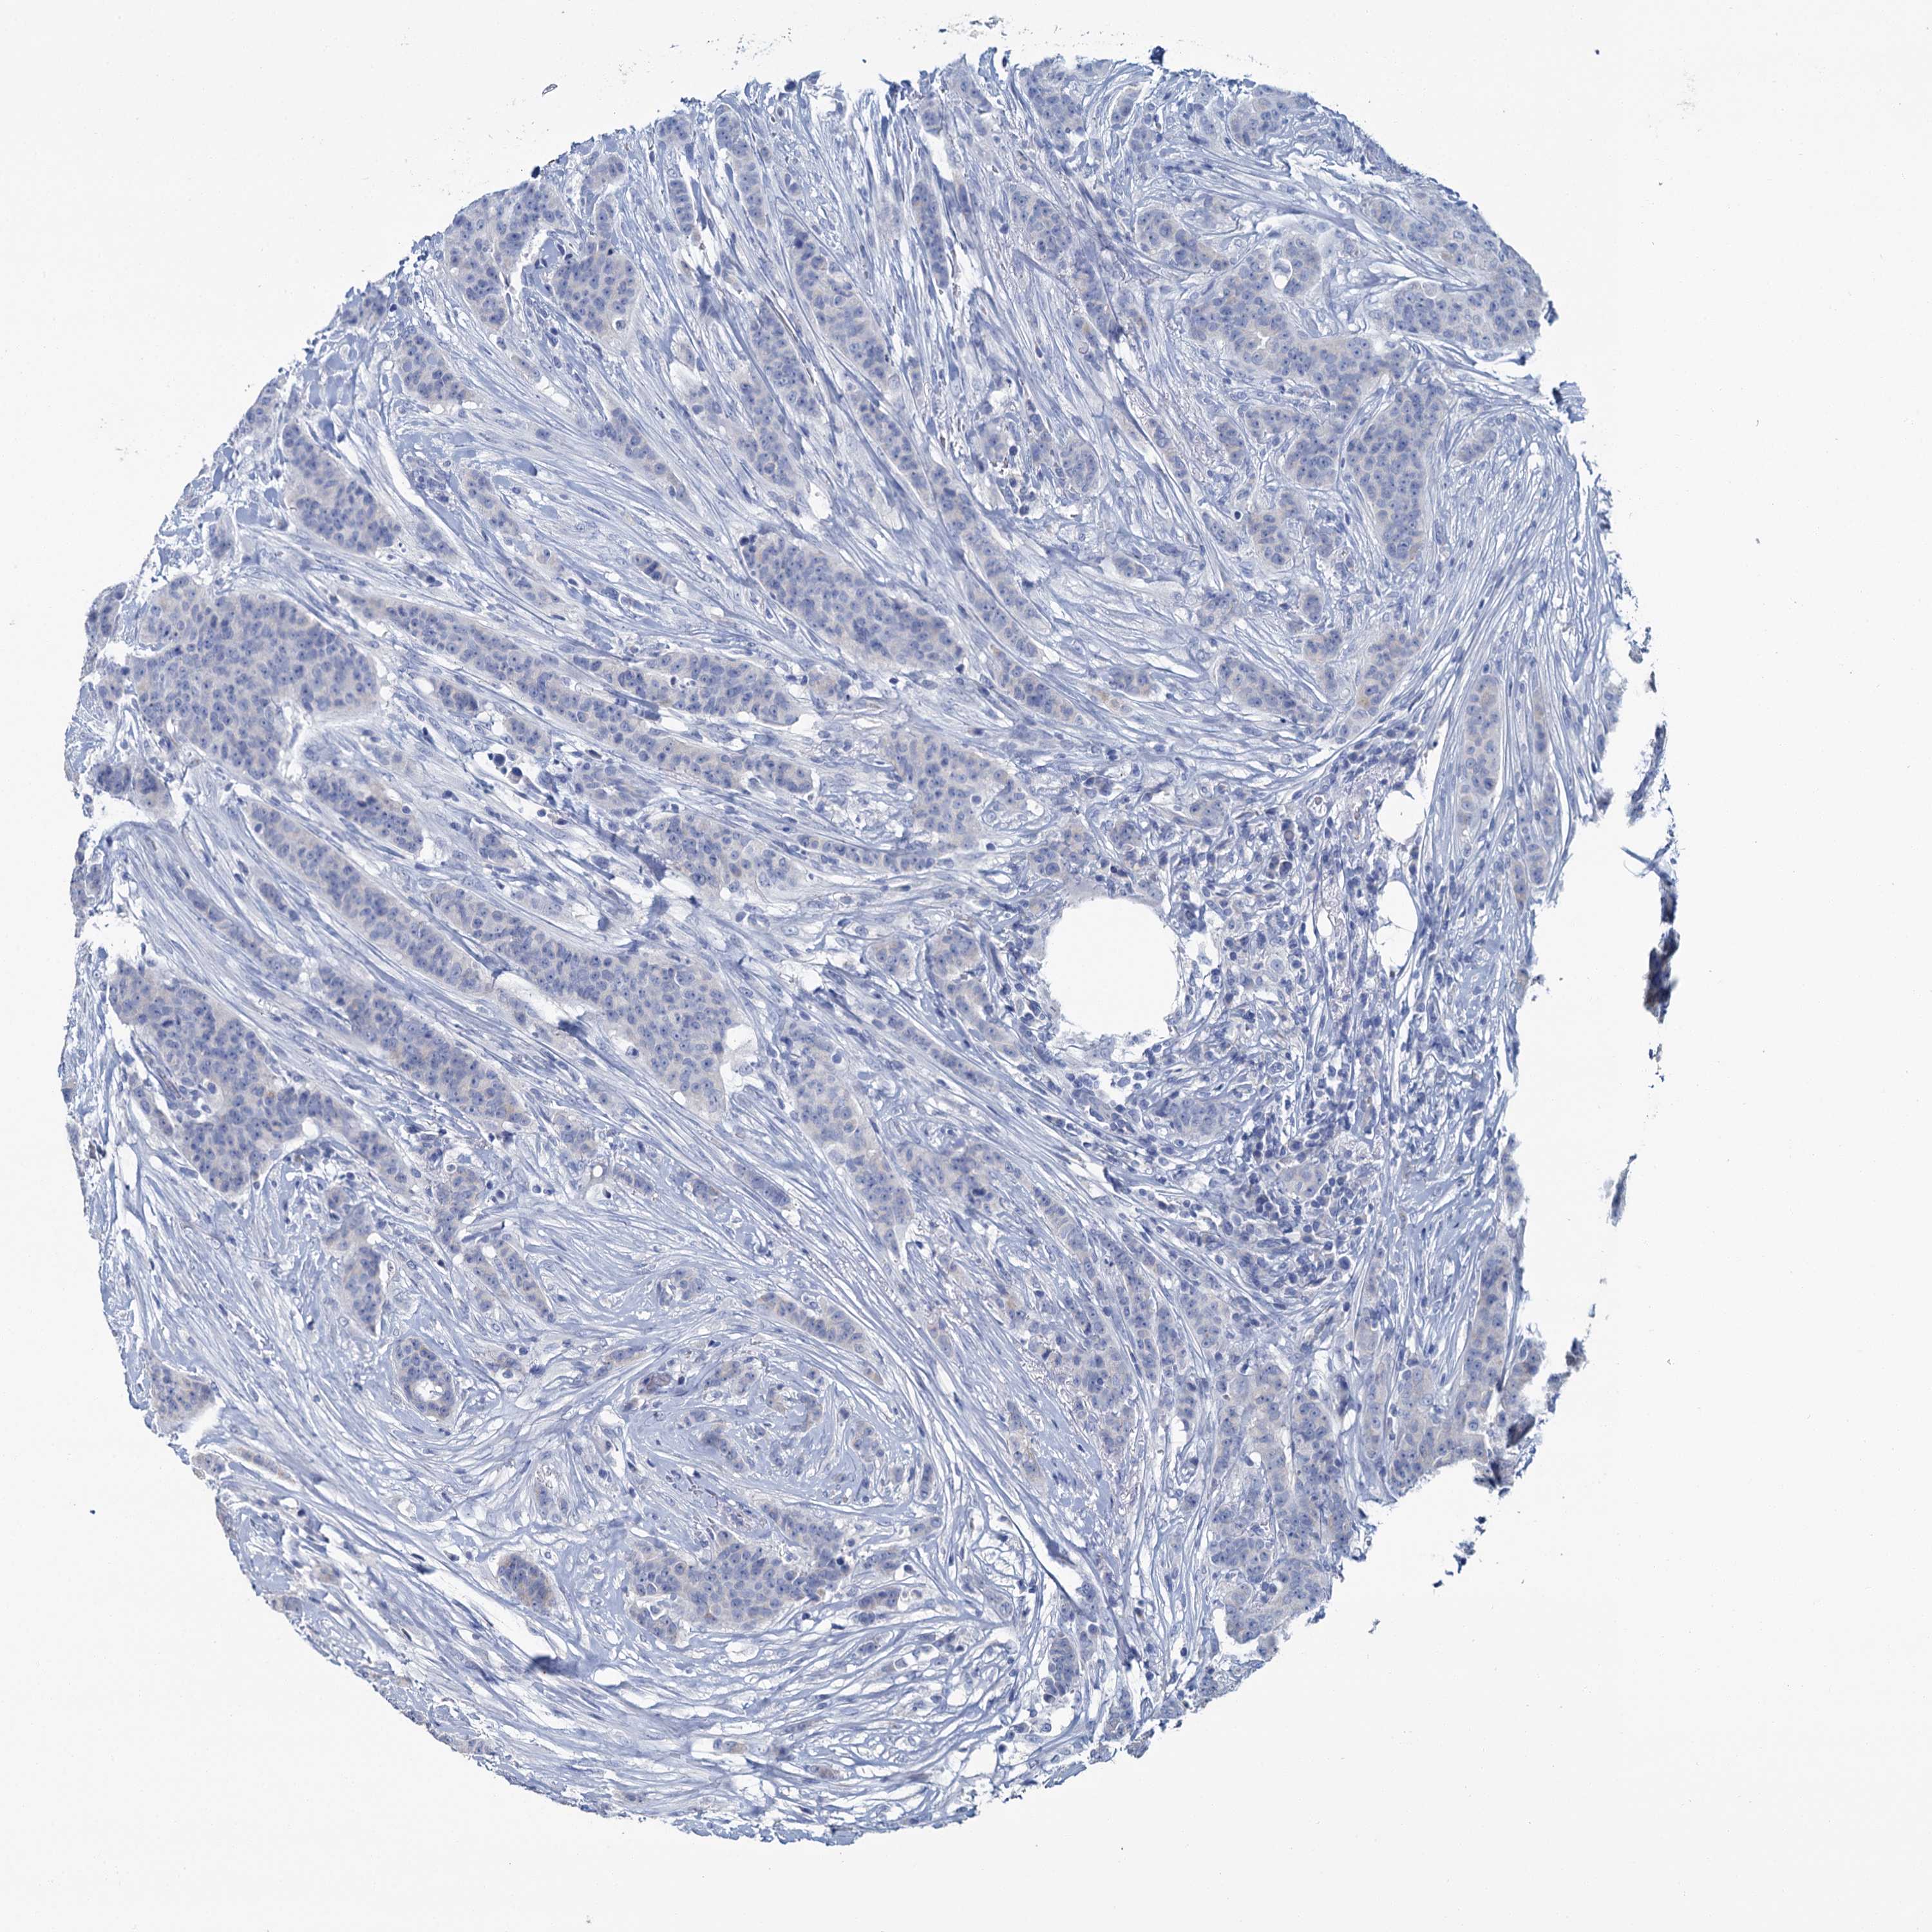

CANCER BREAST CANCER Show tissue menu

Breast cancer

Human cancer